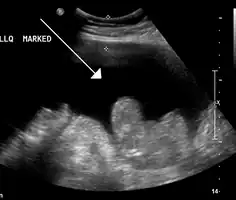

| Turbid peritoneal fluid withdrawn during a diagnostic paracentesis, which is consistent with SPB.[1] | |